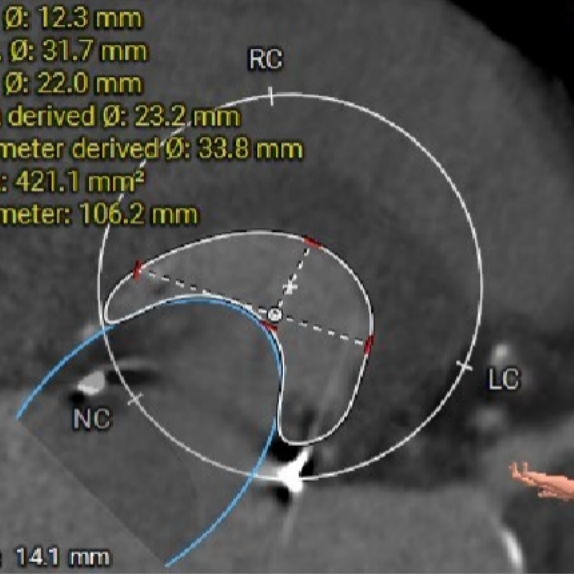

Annulus——内径

Annulus——外径

瓣架高度

Sinotubular Junction

Ascending Aorta

SOV Diameter

Hockey Puck (VR)

LCA Height

RCA Height

冠脉风险:LCA:8.0mm,RCA:11.4mm;外科瓣术后,SOV:34.0*36.3*36.4mm,STJ:33.8mm,冠脉堵塞风险低;

预选瓣膜型号:ScienCrown TAVTA23mm;

选瓣依据:该主动瓣原置换生物瓣为Hancoke II#25,CT测量生物瓣瓣环周长折算直径约22.8mm,瓣架高度约18.0mm;